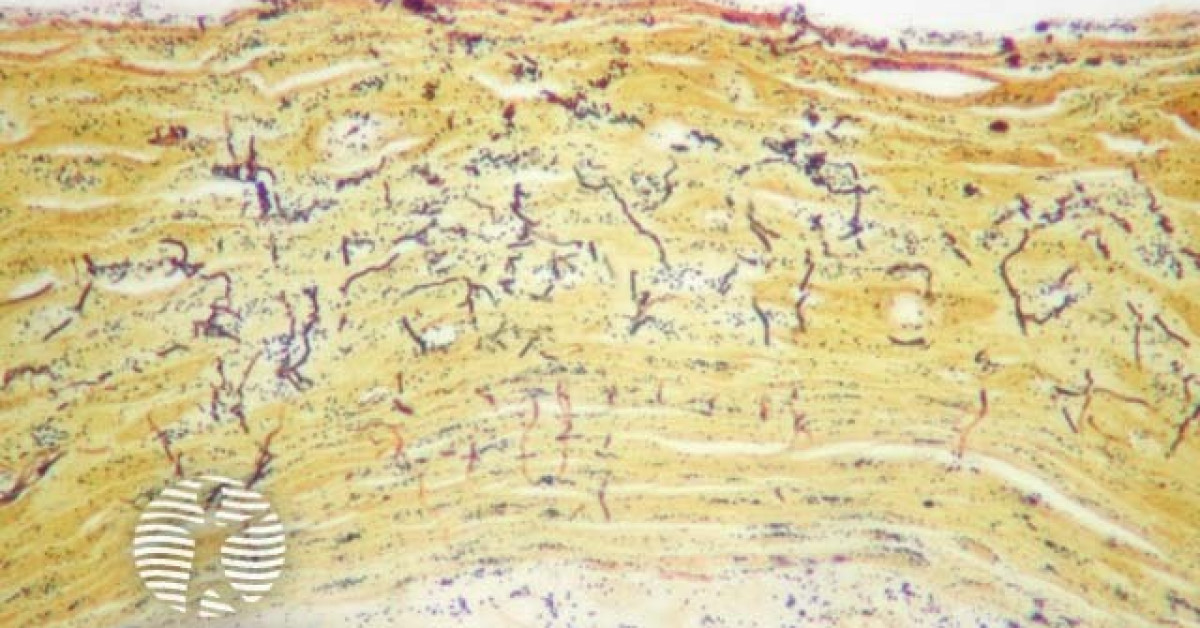

Pitted keratolysis pathology image Pitted Keratolysis Dermnet as with erythrasma, the causative organism of pitted keratolysis is typically a corynebacterium. Other organisms have also been implicated, including. It is associated with hyperhidrosis and occlusive footwear. The pitted keratolysis is secondary to the hyperhidrosis. pitted keratolysis (also known as keratolysis sulcata, keratolysis plantare sulcatum, and ringed keratolysis) is a. pitted keratolysis is a skin disorder. Pitted Keratolysis Dermnet.

This tissue specimen shows signs of Pitted Keratolysis due to a Pitted Keratolysis Dermnet pitted keratolysis is a bacterial infection that causes smelly feet and skin pits. pitted keratolysis causes smelly feet. It is caused by corynebacteria, and possibly dermatophilus. pitted keratolysis is a skin disorder that affects the stratum corneum of the plantar surface and is caused by gram. as with erythrasma, the causative organism of pitted keratolysis is. Pitted Keratolysis Dermnet.

Pitted Keratolysis Histology Pitted Keratolysis Dermnet pitted keratolysis is a bacterial infection that causes smelly feet and skin pits. pitted keratolysis causes smelly feet. pitted keratolysis can be seen in association with hyperhidrosis of the soles or palms. It is caused by corynebacteria, and possibly dermatophilus. Other organisms have also been implicated, including. It is associated with hyperhidrosis and occlusive footwear. as. Pitted Keratolysis Dermnet.